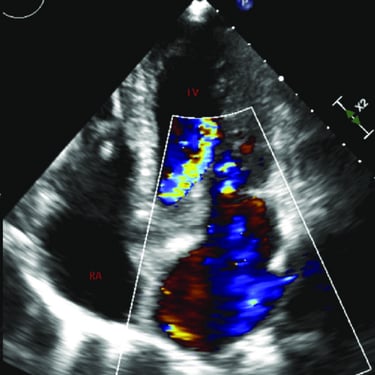

Transthoracic Echocardiogram

An echocardiogram is an ultrasound scan that uses sound waves to create detailed images of the heart, assessing its structure, function, and blood flow to diagnose various cardiac conditions.